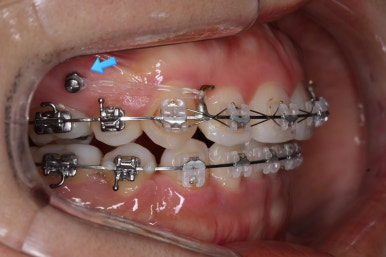

입 속 좌우 모습인데요. 문제점은 다음과 같이 있었어요.

윗니와 아랫니의 교합이 톱니바퀴처럼 맞물리지 않고 1대1 정면으로 맞닿고 있었습니다.

앞니쪽도 보면 윗니와 아랫니의 앞뒤 간격이 크게 차이나는 것을 볼 수 있습니다.

발치교정을 하였을 때, 흔히 나타나는 문제인데 앞니의 각도가 안으로 매우 굽어져 있습니다. 옥니라고 하며 발치를 한 공간을 너무 당겨 넣다보면 발생할 수 있습니다.

3번과 관련하여 더 큰 문제는 다음 사진에서 볼 수 있습니다.

이 후에는 미니스크류를 심어주었어요.

해당 장치를 활용해 윗니를 뒤로 당겨왔습니다.

점점 개선이 되고 있는 모습이 보입니다.

정면으로 맞물렸던 교합도 좋아지고 있으며 이로 인해 자연스레 위아래의 앞뒤 간격도 맞닿게 되고 좁아지고 있습니다.

좌측에서 본 모습도 마찬가지입니다.

발치 후에 남아있던 미세한 공간도 없어졌고 윗니도 후방 이동 되면서 교합이 좋아지고 있습니다.

앞니, 어금니 맞물림이 좋아진 것을 볼 수 있습니다.

안으로 굽었던 옥니의 각도가 역교정으로 다시 회복이 되었습니다.